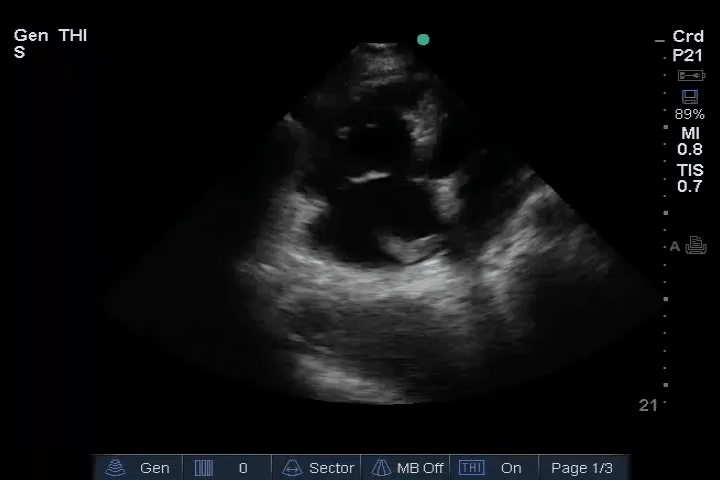

11_Heart_A4CH – Dilated RV, RA embolus

12_Heart_PLAX – Dilated RV, RA embolus